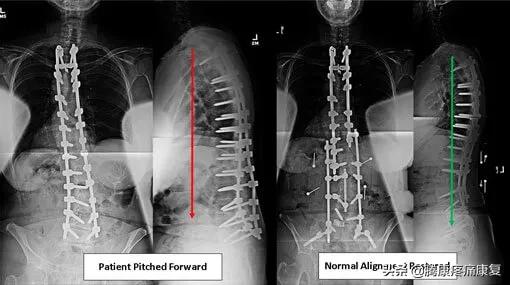

平背表明脊柱失去了正常的生理曲线,正常情况下当我们从侧面观察身体时,矢状轴与垂直方向的对齐不应该超过5MM,而平背综合征的患者,由于重心前移,轴心距垂直距离会超过5MM。

平背会导致脊柱失衡,在站立或行走的时候身体会更倾向于向前倾斜,平背的患者在站立的时候注意力会不集中或站立不直,还会导致背部和腿部持续疼痛。

对于严重的平背综合征患者,需要进行手术,手术的目的是消除患者的疼痛,并以尽可能恢复正常曲线的方式重新调整脊柱。当保守疗法不能改善患者的症状,并且患者的病情似乎一天比一天恶化时,就要进行手术。

对于畸形到开始压迫脊神经,导致背部剧烈疼痛以及麻木、虚弱、刺痛和感觉异常的患者,也需要通过尽可能地重新调整脊柱来减轻症状。